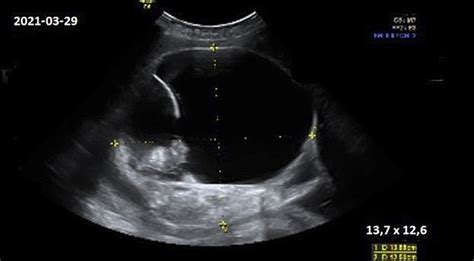

Besivystantis kūdikis toliau auga ir jau pradeda atmerkti akis. Apie 31-34 nėštumo savaitę kūdikis jau gali būti gimdymo padėtyje. Apytikslė gimdymo data yra 40-41 nėštumo savaitė, tačiau daug kas priklauso nuo individualių aplinkybių.

Trečiojo trimestro metu vaisius sparčiai auga ir brandėja. Jo svoris auga - trečiojo trimestro pradžioje jis sveria apie 1 kg, o prieš gimdymą - dažniausiai 3-4 kg. Plaučiai ir nervų sistema toliau brandėja - apie 34-36 savaitę vaisius tampa pakankamai brandus išgyventi už gimdos ribų be didelės medicininės pagalbos. Vaisius įgauna vis daugiau poodinių riebalų - oda tampa lygesnė, mažiau raukšlėta. Aktyvumas didėja, bet vėliau (apie 36-38 savaitę) vaisiaus judesiai gali sumažėti, nes gimdoje lieka vis mažiau vietos. Apie 32-36 savaitę dauguma vaisių apsisuka galvute žemyn - tai vadinama galviniu pirmeigumu, kuris yra palankiausias natūraliam gimdymui. Svarbu kasdien stebėti vaisiaus judesius - staigus ar ilgalaikis jų sumažėjimas gali būti ženklas, kad reikia skubiai kreiptis į gydytoją.